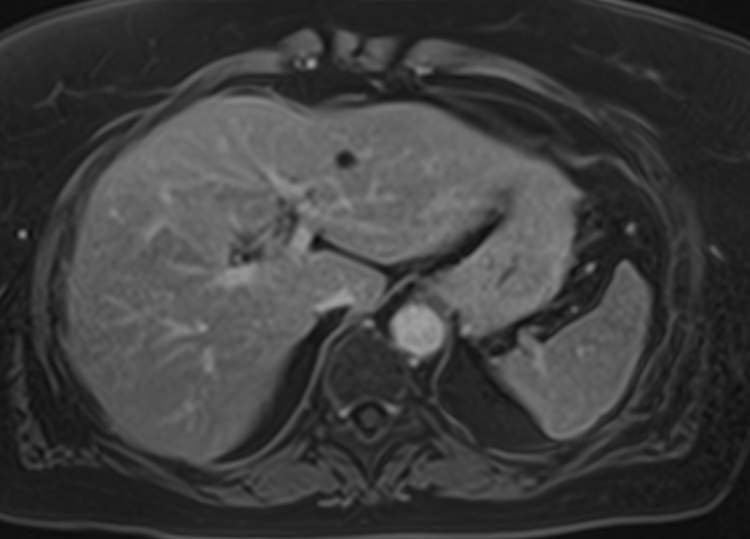

Магнитно-резонансная томография является современным наиболее информативным методом диагностики заболеваний печени. С помощью использования магнитного поля, обладающего высокой индукционной мощностью, МРТ позволяет получать послойные изображения органа и окружающих тканей и выявлять патологические изменения в печени на самых ранних стадиях развития, когда другие методы диагностики не дают результатов.

Для повышения качества визуализации патологических очагов поражения дополнительно применяется контрастное усиление. Для этого в вену вводится контрастный препарат, содержащий гадодиамид (соли металла гадолиния). Контраст позволяет оценить степень и характер васкуляризации в очагах поражения. Методика применяется для ранней диагностики как первичных опухолей печени, так и метастатического поражения, что имеет решающее значение для проведения своевременного лечения.

В клинике «Доступная медицина» исследование проводится на современном высокопольном томографе экспертного класса TOSHIBA VANTAGE TITAN 1,5 Тесла. Аппарат послойно сканирует исследуемую зону в трех плоскостях с шагом от 1 мм, при этом получая данные о структуре органа в мельчайших подробностях. Инновационные компьютерные программы реконструируют данные в трехмерные модели органа, отображающие состояние не только паренхимы печени, но и внутрипеченочных желчных протоков и сосудистой системы.